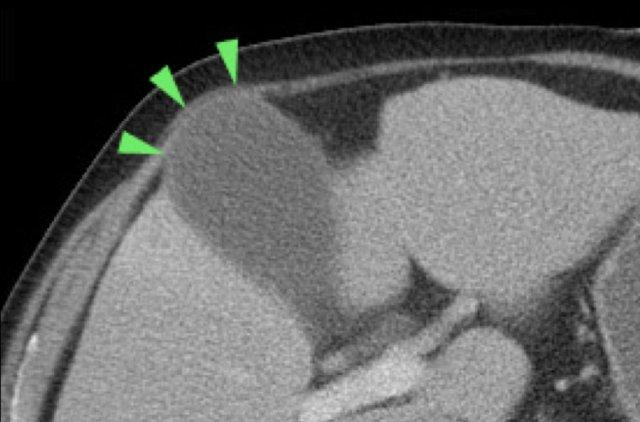

Không hiếm gặp trường hợp phình to túi mật được phát hiện trên CT scan (hình), nhưng siêu âm bổ sung thường rất hữu ích trong những trường hợp này.

Hình ảnh của một bệnh nhân được nghi ngờ lâm sàng là thủng dạ dày.

CT cho thấy một số sỏi trong túi mật có hình dạng tròn.

Siêu âm bổ sung xác nhận rõ ràng tình trạng phình to túi mật (đầu mũi tên).